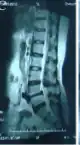

MRI of the lumbar spine, intervertebral disc degeneration